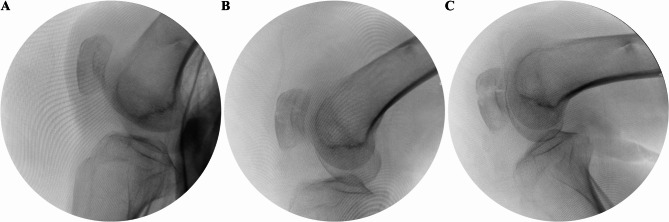

Methods: Fourty-two patients with transverse patellar fractures participated in this study, twenty of whom underwent minimally invasive surgery and twenty-two underwent open surgery. In the minimally invasive group, intraoperative tension band internal fixation was performed using Nice knot assisted reduction. Postoperative knee pain, knee mobility, operative time, complications, number of intraoperative C-arm fluoroscopy scans, length of hospital stay (in days), and Bostman score were recorded for each patient in both groups.